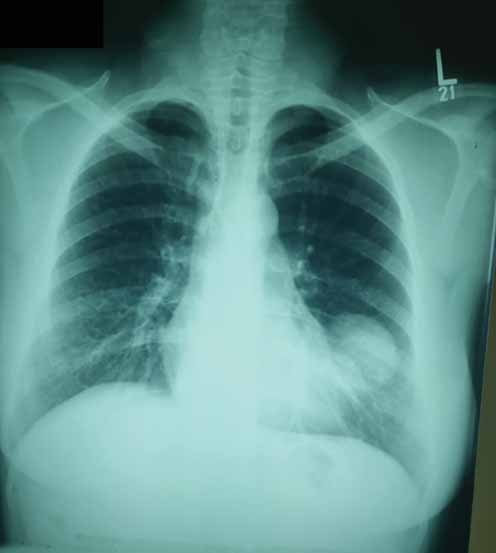

Biểu hiện chính của bệnh được phát hiện ngẫu nhiên trên các hình ảnh chụp X-quang. Tuy nhiên, bệnh nhân có thể trải qua các triệu chứng như ho, ho ra máu, đau ngực hoặc tràn khí màng phổi. Các hình ảnh chụp X-quang của bệnh nang sán phổi khác nhau giữa E. granulosus và E. multilocularis. Bệnh nang sán do E. granulosus,khi các nang chưa bị vỡ, sẽ tạo ra các nốt hoặc khối có bờ mịn và không bị vôi hóa. Ngược lại, loài E. multilocularis gây ra bệnh Echinococcosis phế nang (Alveolar Echinococcosis) và trên hình ảnh chụp X-quang hoặc CT scan, bệnh này xuất hiện dưới dạng các nốt hoặc khối có hình dạng tạo thùy và có sự vôi hóa.

Các đặc điểm chính của nang sán trên hình ảnh X-quang bao gồm: dấu meniscus, dấu bán nguyệt, dấu Cumbo, dấu vỏ hành tây, dấu hoa súng và dấu khối trong khoang. Một trong những dấu hiệu kinh điển trên hình ảnh X-quang của nang sán là một vùng sáng tròn rõ ràng trong phổi, có hoặc không có sự vôi hóa(Hình 6). Bệnh nang sán phổi có thể bị nhiễm trùng thứ phát và trên hình ảnh X-quang ngực có thể xuất hiện u nang và mức dịch khí (Hình 7).

Hình 6.Chụp X-quang phổi thông thường cho thấy có  một vùng sáng tròn rõ ràngnằm ở vùng thấp bên trái của phổi.